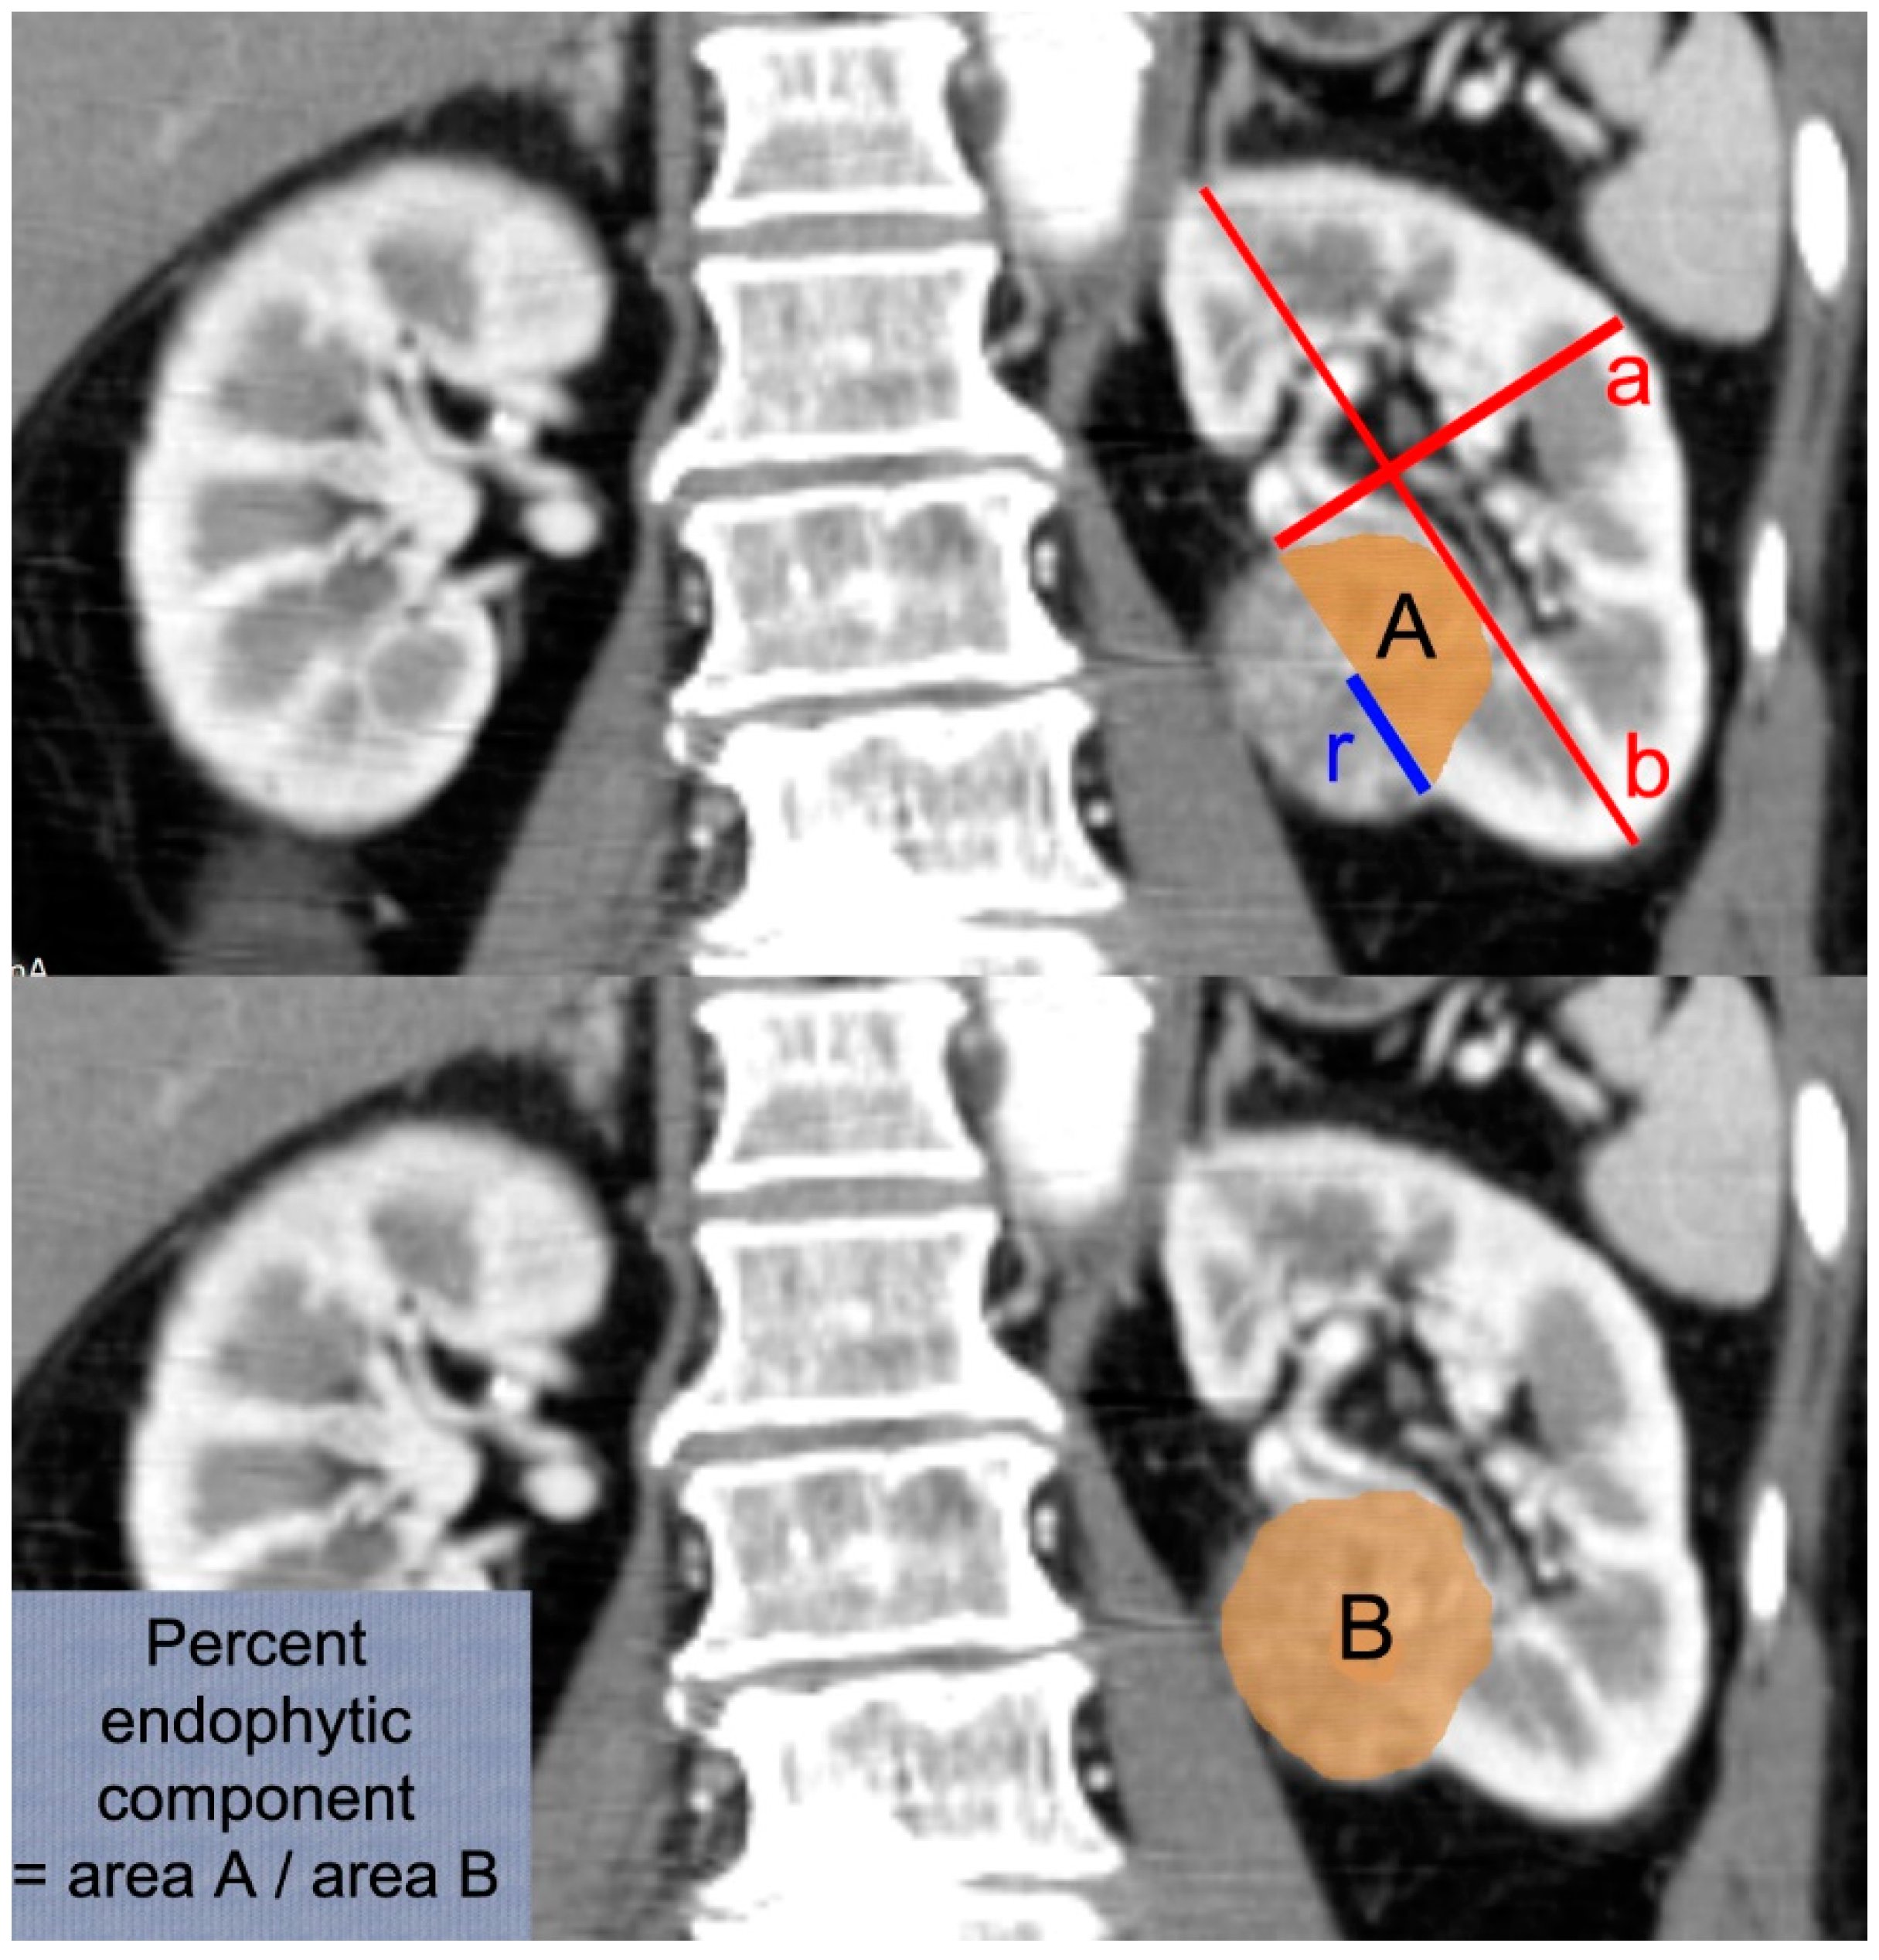

- Ding, Y.; Kong, W.; Zhang, J.; Dong, B.; Chen, Y.; Xue, W.; Liu, D.; Huang, Y. Spherical cap surface model: A novel method for predicting renal function after partial nephrectomy. Int. J. Urol. 2016, 23, 667–672. [Google Scholar] [CrossRef] [PubMed][Green Version]